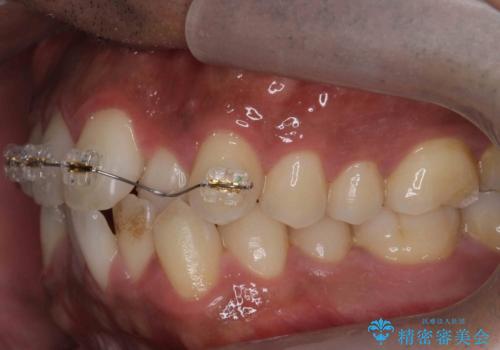

上はワイヤー部分矯正、下はインビザラインの部分矯正コースを行いました。

インビザラインだけでも治療は可能ではあると思いますが、ライトパッケージでは難しいと思います。

また、入れ替えを行う間左上の前歯だけで咬まなくてはならない状況になるため、マウスピース矯正単独で行うと時間がかかり、最悪神経が失活することもありますのでワイヤーがお勧めです。